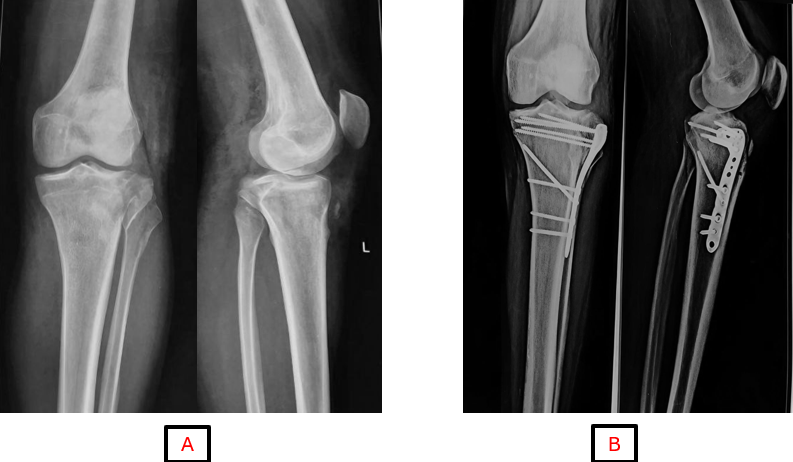

The mean range of motion at the final follow-up was recorded at 125° with a standard deviation of 9.90°. A significant improvement in range of motion was noted between the first and second follow-ups, followed by a gradual enhancement in subsequent assessments. All patients achieved a range of motion exceeding 90° during the final evaluation. Fractures categorized as Schatzker types II and III were treated with a single LCP (Fig. 1), while dual plating was required for nearly all cases of types V and VI (Fig. 2). In addition, three cases of type IV fractures were fixed with dual plating, and one type V fracture was stabilized utilizing triple plating.

Figure 1: (a and b) Pre-operative and 6-month follow-up radiograph of Schatzker type II proximal tibia fracture.